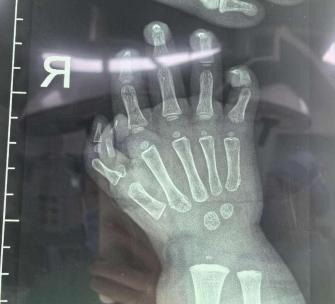

女童长了2根拇指 医生“移花接木”巧妙矫形

不到2岁女童多指畸形像“螃蟹爪”,医生“移花接木”将多指的部分功能融入正常手指。近日,北京儿童医院烧伤整形外科王燕妮团队成功完成一例复杂多指畸形矫形手术。

花花(化名)天生多指畸形,右手有两个拇指。其中一个拇指没有感知和功能;另一个拇指虽然能动,但是细小且严重偏斜。这不仅影响外观,更重要的是影响了她的手部功能。面对这一多指畸形患儿,北京儿童医院烧伤整形外科副主任王燕妮(主持工作)带领团队商讨手术方案后,决定巧妙地来一次“移花接木”,帮助花花截除多出来的拇指,并恢复其中一个拇指的神经和功能。

在显微镜下,这场精细的手术开始了。王燕妮团队先将那个无功能的小拇指制成了一个带有血管、神经和部分指骨的拇甲瓣,然后巧妙地将其嵌入到有功能的拇指旁边,两甲床融合变宽,一系列操作让拇指及指甲变得像正常拇指一样饱满。就这样,两个拇指被医生巧妙地融合在了一起。随后,医生又通过截骨手术矫正了拇指的偏斜。

这台手术不仅在外观上大大优于传统的切除手术,而且在功能上,拇指的肌腱、关节、指骨也都得到了保留,血管和神经的功能也得到了保障。术后,烧伤整形外科还为花花开展了瘢痕防治和手部功能康复训练。